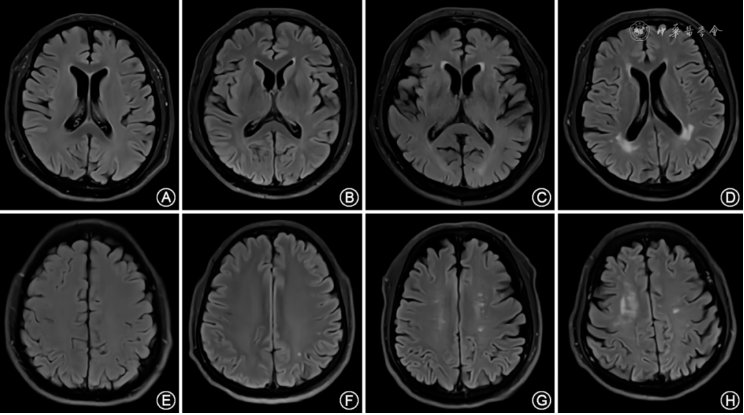

于PSG检查前后2周内完成,采用3.0 T MR扫描仪(Siemens,Prisma,德国)进行图像采集。扫描序列包括:常规T1加权像序列(T1WI;TR:2 300 ms,TE:2.34 ms)、T2加权像序列(T2WI;TR:4 500 ms,TE:98 ms)、液体衰减反转恢复序列(FIAIR;TR:9 000 ms,TE:81 ms),层厚4 mm。由固定1位对受试者PSG结果不知情的影像科医师,根据颅脑T2WI和FIAIR序列,使用Fazekas视觉分级法对受试者的WMH进行评价。Fazekas评分标准如下[9]:PWMH评分:无病变记为0分(图1A);存在帽状或者铅笔样薄层病变记为1分(图1B);存在病变呈光滑的晕圈记为2分(图1C);存在不规则的PWMH,延伸到深部白质(图1D),记为3分。DWMH:无病变记为0分(图1E);点状病变记为1分(图1F);病变开始融合记为2分(图1G);病变大面积融合记为3分(图1H)。PWMH和DWMH评分之和即为WMH总分,根据总分进行Fazekas分级:总分0分为Fazekas 0级,1~2分为Fazekas 1级,3~4分为Fazekas 2级,5~6分为Fazekas 3级。

图1 Fazekas视觉分级法的脑白质高信号(WMH)评分示意图 图A、B、C、D分别为脑室旁WMH 0、1、2、3分的示意图,图E、F、G、H分别是深部WMH 0、1、2、3分的示意图。以上各图均取自本研究患者中的MRI FLAIR序列。其中图D来自1例41岁的睡眠呼吸暂停(OSA)患者,呼吸暂停低通气指数(AHI)28.1次/h,蒙特利尔认知评估量表(MoCA)测试 26分,可见脑室旁不规则的高信号延伸到深部白质;图H来自1例42岁的OSA患者,AHI 62.8次/h,MoCA 测试25分,可见深部白质区域大面积的高信号融合